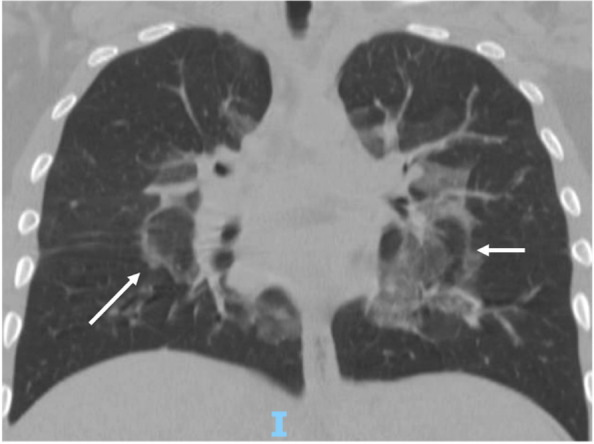

Specifically, EVALI should be suspected in a patient with a history of vaping presenting with respiratory symptoms such as shortness of breath, cough, chest pain, pleuritic chest pain and haemoptysis and/or gastrointestinal symptoms such as nausea, vomiting, diarrhoea and abdominal pain. Systemic symptoms such as fever, tachycardia and tachypnoea may be present. Hypoxemia may be present and progression to respiratory failure is common [ref. 12]. Bloodwork doesn’t show specifical evidences, nevertheless, some elements may be evocative of EVALI: a non-specific raise of the inflammation indexes may be detected. Blood exams may also be useful to exclude other processes in the differential diagnosis [ref. 13, ref. 14]. The radiological evaluation in patients with suspected EVALI generally shows diffuse hazy or consolidative opacities at the chest radiograph. Chest CT would typically show a ground glass imaging with spare of the sub pleural space [ref. 15]. GGOs (Ground-glass opacification) are common, and the most useful imaging features to help differentiate EVALI from COVID-19 are subpleural sparing of pulmonary opacities (GGOs) and centrilobular nodules (infrequent in COVID-19) (Fig. 2). In our case there was no thickening of the interlobular septa, but the reversed halo sign was present (atoll sign) (Fig. 3), which is characterized by the presence of a central ground-glass opacity surrounded by dense consolidation of crescentic shape or complete ring (sign present in late phase COVID-19 and typical of BOOP (bronchiolitis obliterans organizing pneumonia) and Wegener). These findings are consistent with diffuse alveolar damage, as seen in acute respiratory distress syndrome. The radiological findings vary according to the underlying histopathological process. Histology isn’t routinely performed, several pathologic patterns of lung injury have been reported in the setting of vaping such as lipoid pneumonia, diffuse alveolar damage, acute eosinophilic pneumonia, organizing pneumonia, diffuse alveolar haemorrhage, respiratory bronchiolitis interstitial lung disease, hypersensitivity pneumonitis and giant cell interstitial pneumonia, prompting the heterogeneity of the underlying disease processes. [ref. 16–ref. 21]. At the broncho alveolar lavage fluid (BAL) of affected patients the most commonly found substances appeared to be tetrahydrocannabinol (THC) and/or vitamin E acetate, the presence of lipid-laden macrophages seen with oil red O staining has been reported as well [ref. 22, ref. 23]. Vitamin E had been recently looked at as possible culprit in the pathogenesis of EVALI as multiple studies report its presence in the BAL samples from patients affected from EVALI, while it hasn’t been detected in healthy individuals [ref. 9, ref. 23]. Vitamin E is often used as a thickening agent of illegal THC containing vapes. According to the American public health authorities, in order to formalise the diagnosis of EVALI, vaping should be present within 90 days prior to the symptom onset, an underlying infectious cause needs to be ruled out and there should be no evidence of other plausible diagnoses (e.g. cardiac, rheumatologic or neoplastic processes) [ref. 9, ref. 24].